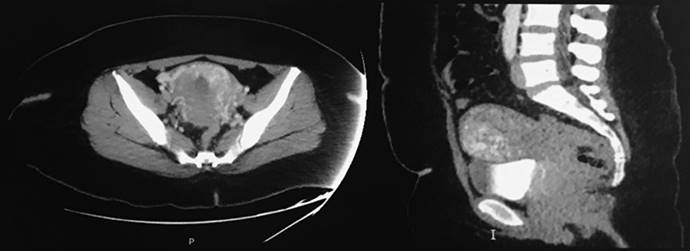

La tomografía toracoabdominopélvica simple y contrastada reportó: múltiples nódulos pulmonares de distribución dispersa, hígado y ovarios normales. La tomografía de cráneo simple y contrastada no informó anormalidades. Figura 2

Figura 2 Tomografía toracoabdominopélvica con múltiples nódulos pulmonares de distribución dispersa y de cráneo simple normal.

En este caso se trató de un coriocarcinoma por lo que luego de diagnosticarlo y cohibir el sangrado y empezar la reposición sanguínea hay que determinar la extensión del tumor con una radiografía de tórax, tomografía computada y resonancia magnética que, en este caso, permitió estadificar el tumor en estadio III, por su invasión al pulmón, con múltiples focos de metástasis.